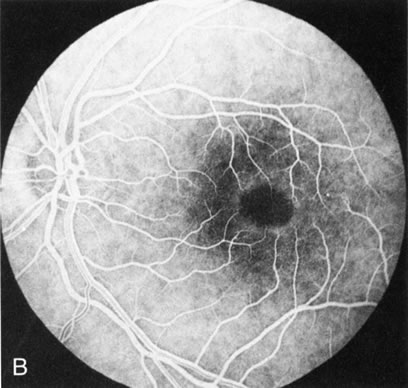

In Stargardt's disease, thes most common hereditary macular dystrophy, FA has a variety of functions. In the mildest fundus presentation, with visual symptoms and visual function out of proportion to the observed maculopathy, FA can confirm or even make the diagnosis and can avoid a mistaken diagnosis of malingering, hysteria, or central nervous system disease (Fig. 9A and B). When a maculopathy is present without surrounding parafoval flecks, FA may show patchy areas of transmission hyperfluorescence in the posterior pole, indicating a more diffuse involvement (Fig. 9C and D).

Fig. 9. Stargardt's disease–fundus flavimaculatus. The mild maculopathy (without parafoveal flecks) (A) is confirmed by the angiogram (B). The relative absence of the underlying choroidal flush, resulting in an easier visualization of the overlying retinal capillary circulation, has been referred to as the “silent” or “dark” choroid, and is considered a common finding in this disease. The diagnosis is confirmed in an individual with a pigmentary maculopathy without flecks (C). Here the angiogram demonstrates widespread transmission hyperfluorescence and a “silent” or “dark” peripapillary area (D). When the posterior pole shows multiple yellowish-white flecks (E), the angiographic findings do not necessarily correspond to the flecks (F). It should also be noted that despite the widespread abnormalities, the background choroidal fluorescence is normal.

In a large majority of patients (86% in one study),20 there is an absence or decrease in the background choroidal fluorescence (which is referred to as the “silent” or “dark” choroid) (see Fig. 9B). This warrants special attention because it occurs so frequently, is rarely found in other retinal disorders,21 and may be related to histopathology that shows an increase in lipofuscin in the RPE.22